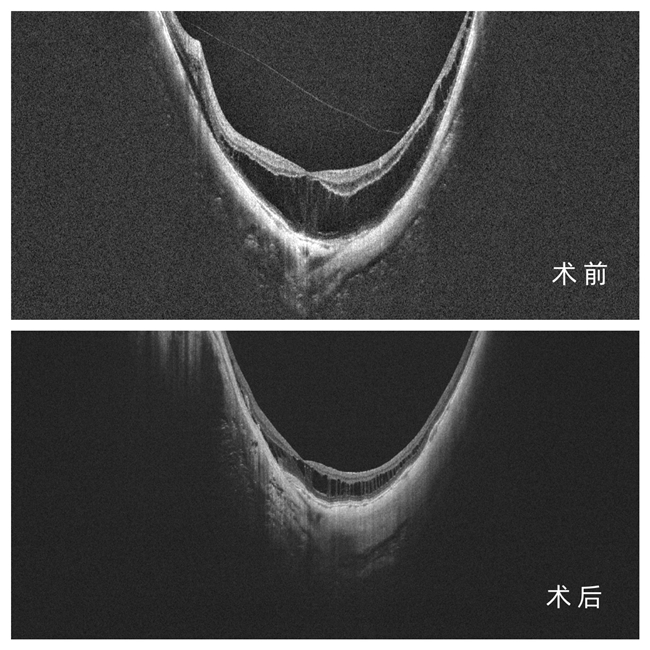

在做好完备术前准备后,5月,谷威院长顺利为施先生成功实施左眼后巩膜加固术。一个月后,谷威院长再次为施先生开展左眼视网膜修复联合白内障手术,并同步完成右眼白内障手术,术后施先生双眼视力已明显提升。

8月复查时,施先生迎来 “双重惊喜”:视力上,右眼从 0.01 恢复至 矫正视力0.1,左眼从 0.07 提升至矫正视力 0.5,完全能满足日常生活需求;左眼视网膜复位显著,视网膜劈裂问题成功解决;更令人振奋的是—— 左眼眼轴从 33.98mm “回缩” 至 33.70mm,而未做加固术的右眼眼轴则从 32.74mm 增长至 33.20mm。这一鲜明对比,印证了后巩膜加固术在控制眼轴增长、甚至实现“回缩”中的作用。